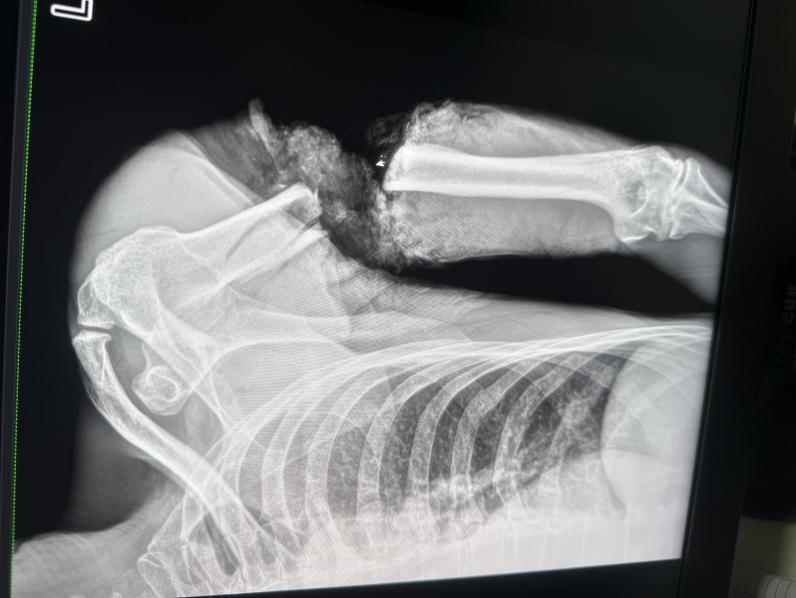

CT图像下冉文海断臂情况非常严峻。张晓锐供图

“左上臂已经完全离断,上臂上段呈环形开放性伤口,仅仅部分皮肤、肌肉相连,重要血管神经毁损长度达8厘米,污染物深入肌理,这比两年前病例更凶险的高位离断。”手术医师张晓锐回忆,团队果断启用“创伤优先分级救治系统”,在患者仍处于休克状态时,已同步完成离断肢体低温处理、三维CT血管成像和手术方案制定。